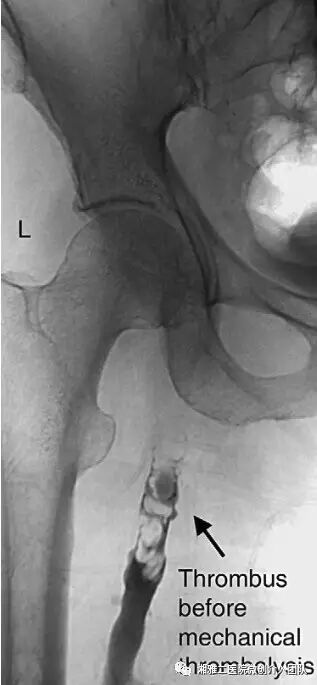

第六,造影随访评估后,采用8f导引导管进行血栓取出术,最大限度的取出血栓

上图为我们使用8F导引导管取出的血栓